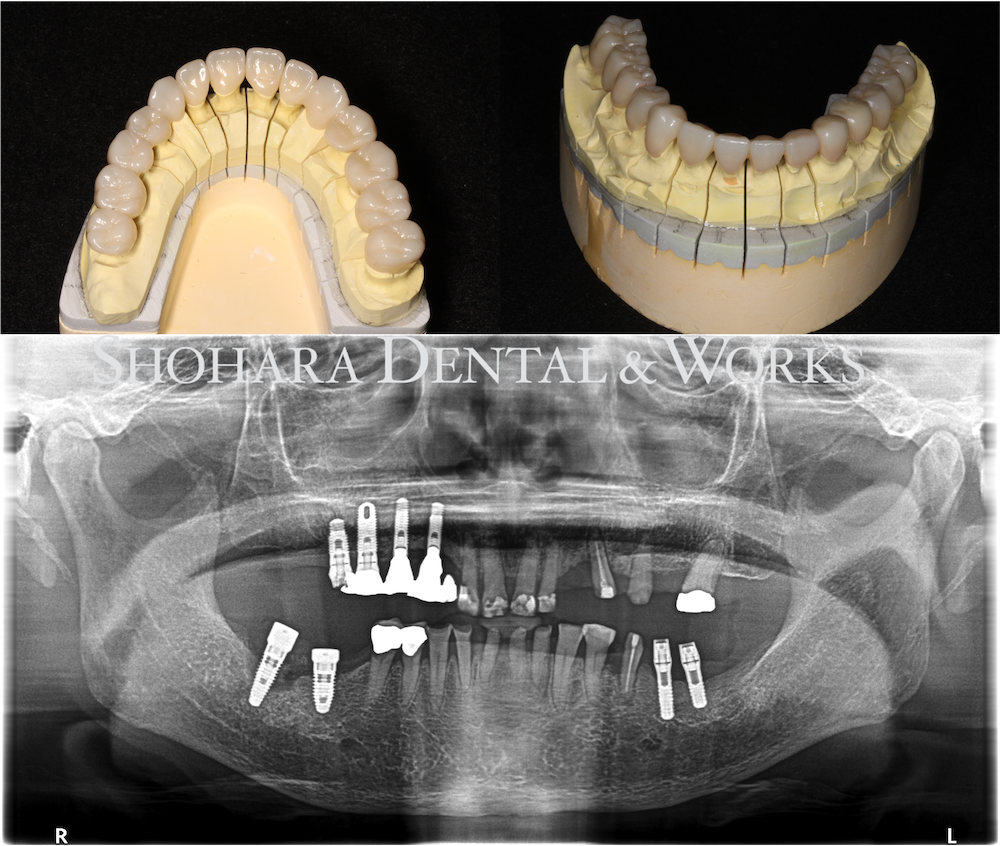

補綴物写真、レントゲン写真

| 治療説明 | 既存のインプラントを利用し上部構造の再製作と、咬合再構成により全顎補綴を行った。 |

噛み合わせが強いので、ジルコニアのブリッジ、クラウンを装着しました。

今回、ご高齢であるので、インプラントの再手術は行わずに、既存のインプラントを利用し噛み合わせを再構築(咬合再構成)することにしました。まず、奥歯のに仮歯を入れて、下がってしまった噛み合わせを上げて戻します。また、全ての歯を再形成し、仮歯を入れさせていただきました。新しい噛み合わせで、約2ヶ月過ごしていただいて、不快症状がないことを確認して、口腔内スキャナーで型取りを行いました。